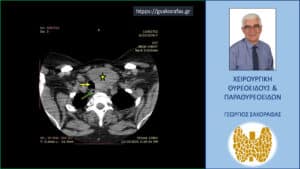

Αξονική τομογραφία και πάλι στο ύψος του τραχήλου αλλά σε χαμηλότερο επίπεδο. Κίτρινος αστερίσκος – ο ευμεγέθης όζος, κίτρινο βέλος – η τραχεία και πάλι απωθούμενη προς τα δεξιά.